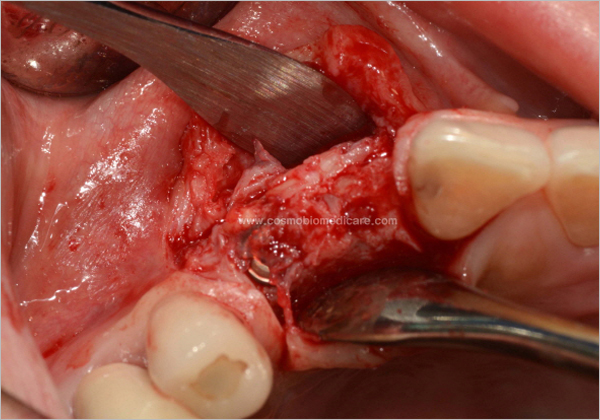

Clinical Cases

• Case1

• Case2

• Case3

• Case4

• Case5

• Case6

• Case7

• Case8

• Case9

• Case10